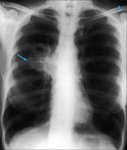

Radiografía de tórax que muestra un carcinoma hiliar izquierdo (flecha)

De: E. Dick, Student BMJ. 2000;8:358-360